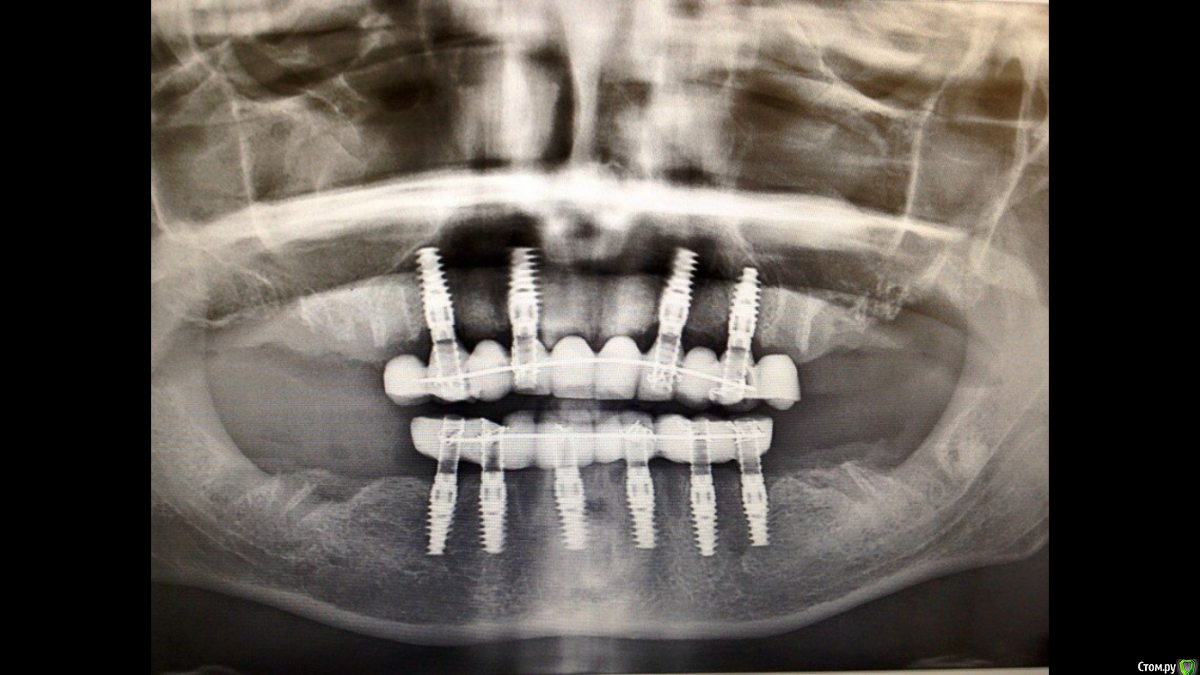

Doc Опубликовано 12 апреля, 2015 Поделиться Опубликовано 12 апреля, 2015 Вообще некоторых я бы послал к Мало поучиться.А то вот такое называют "все на четырех". А это, как бы помягче выразиться, не совсем то... Ссылка на комментарий

Doc Опубликовано 12 апреля, 2015 Поделиться Опубликовано 12 апреля, 2015 Выше приведена времянка (надеюсь), так что есть шанс, что мы не так поняли.А вот тут готовая работа. Тоже есть вопросы. Называют это "все на четырех". Ссылка на комментарий

Evikrol Опубликовано 13 апреля, 2015 Поделиться Опубликовано 13 апреля, 2015 Выше приведена времянка (надеюсь), так что есть шанс, что мы не так поняли.А вот тут готовая работа. Тоже есть вопросы. Называют это "все на четырех". Снимок экрана 2015-04-12 в 22.03.47А вообще что это на последней фото? Несъемный-съемный протез, это постоянная работа не временная? А гигиена как? Ссылка на комментарий

Doc Опубликовано 13 апреля, 2015 Поделиться Опубликовано 13 апреля, 2015 А вообще что это на последней фото? Несъемный-съемный протез, это постоянная работа не временная? А гигиена как?написали, что это условно-несъемный протез по системе "все на четырех". Подробностей не знаю, не видел. Мне просто прислали это с вопросом что общего это имеет с концепцией? На мой взгляд ничего. Ссылка на комментарий

doctore Опубликовано 13 апреля, 2015 Поделиться Опубликовано 13 апреля, 2015 Я помогу с ответами пожалуй )) Первое оптг -работа Макса Копылова - наверху будет доставлено еще 2 винта в дистальных отделах. Сейчас стоит временная конструкция.Вторая оптг- моя работы. Условно сьемный протез.Какие вопросы к гигиене? 1 Ссылка на комментарий

Doc Опубликовано 13 апреля, 2015 Поделиться Опубликовано 13 апреля, 2015 Я помогу с ответами пожалуй )) Первое оптг -работа Макса Копылова - наверху будет доставлено еще 2 винта в дистальных отделах. Сейчас стоит временная конструкция. Вот как полезна осторожность! Не зря я написал, что возможно мы не все знаем! В таком случае Вы меня успокоили. А то мне это показали как все на четырех. Вторая оптг- моя работы. Условно сьемный протез.Какие вопросы к гигиене?К гигиене не мой вопрос был, у меня вопросов нет, не видел протеза. А вот почему Вы это назвали "все на четырех"? Ведь это близко не лежало к нашему товарищу Мало и его концепции. Я как-то в приличном обществе сказал фразу "сделал все на шести", так меня заклевали за использование неправильных определений, а то была просто аналогия-калька. Ссылка на комментарий

Romanson Опубликовано 14 апреля, 2015 Поделиться Опубликовано 14 апреля, 2015 Вообще некоторых я бы послал к Мало поучиться.А то вот такое называют "все на четырех". А это, как бы помягче выразиться, не совсем то... IMG_2052.PNGDoc, расскажите пожалуйста, почему эта работа или та что ниже не соответствует концепции "все на 4х?" И, если есть такая возможность, объясните пожалуйста, чем ещё концепция "all in 4" отличается от просто четырех имплантов на одной беззубой челюсти? Ссылка на комментарий

Doc Опубликовано 14 апреля, 2015 Поделиться Опубликовано 14 апреля, 2015 Doc, расскажите пожалуйста, почему эта работа или та что ниже не соответствует концепции "все на 4х?" И, если есть такая возможность, объясните пожалуйста, чем ещё концепция "all in 4" отличается от просто четырех имплантов на одной беззубой челюсти?Потому что концепция совсем другая и подразумевает установку двух дистальных имплантатов под углом с использованием специальных угловых абатментов. Я где-то на форуме выкладывал уже подобные работы, поищите, там все ясно и понятно. Что касается верхней работы, то как благополучно выяснилось, там планируется добавить еще два имплантата и тот факт, что это работа Максима Копылова уже гарантирует, что она будет сделана по всем правилам. Максим не тот человек, чтобы делать всякую ерунду. Я не зря предположил, что мы чего-то про эту работу не знаем. Ну а нижняя работа, как я понял, уже окончательная и там доктор рассчитывает на верхний съемный протез и что нагрузка будет минимальная, потому хватит и четырех имплантатов. Скорее всего так и есть, и при адекватном осторожном использовании эта работа простоит дольше, чем пациент проживет, но это совсем не "все на четырех", т.к. это уже торговая марка и она подразумевает определенный протокол. Ссылка на комментарий